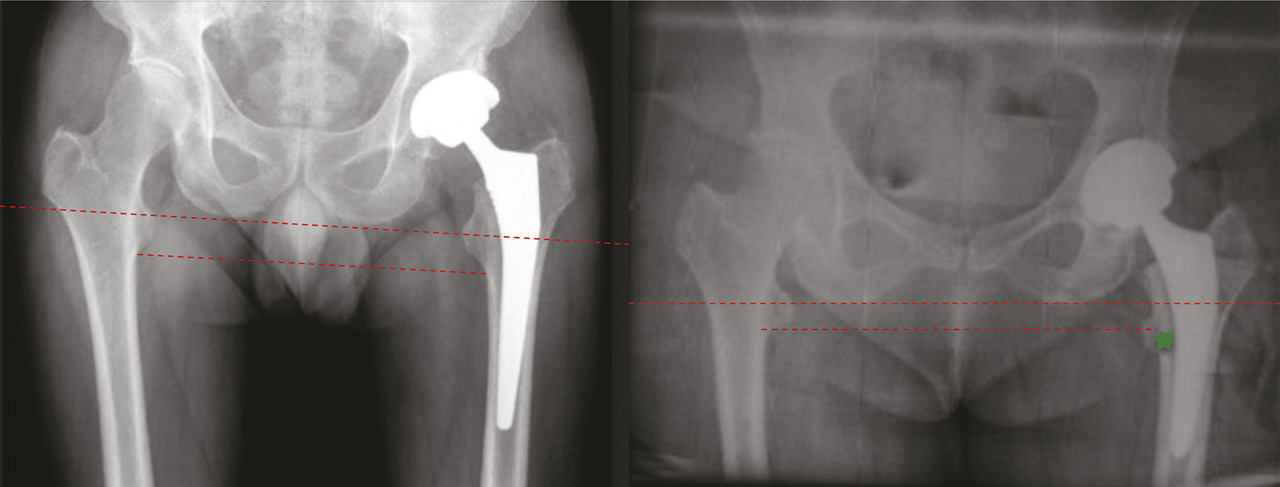

Le diagnostic d’inégalité vraie de longueur des membres inférieurs se fait généralement au moyen de clichés radiographiques. Idéalement, il s’agit de clichés corps entier, avec dorénavant des systèmes d’évaluation très précis tels que le dispositif EOS. Ce dispositif, permettant l’acquisition simultanée de deux clichés de face et de profil, chez un patient en position assise ou debout, limite la dose de rayons X absorbée par le patient et trouve tout particulièrement son indication en orthopédie, permettant notamment une reconstitution 3D des membres inférieurs ou de la colonne vertébrale. À défaut, une radiographie du bassin de face (v. figure ) permet une évaluation approximative en comparant des repères anatomiques fixes au niveau du bassin et sur chaque fémur. Cliniquement, cette évaluation doit idéalement s’effectuer sur un patient en décubitus dorsal, genoux étendus avec les pieds en rotation neutre, puis en mesurant la distance entre les épines iliaques antérosupérieures et les malléoles internes de chaque membre. Une évaluation est également possible sur un patient debout en plaçant une talonnette de taille adaptée sous le membre semblant plus court, après avoir éliminé une attitude vicieuse venant compenser l’inégalité de longueur.

Le diagnostic d’inégalité vraie de longueur des membres inférieurs se fait généralement au moyen de clichés radiographiques. Idéalement, il s’agit de clichés corps entier, avec dorénavant des systèmes d’évaluation très précis tels que le dispositif EOS. Ce dispositif, permettant l’acquisition simultanée de deux clichés de face et de profil, chez un patient en position assise ou debout, limite la dose de rayons X absorbée par le patient et trouve tout particulièrement son indication en orthopédie, permettant notamment une reconstitution 3D des membres inférieurs ou de la colonne vertébrale. À défaut, une radiographie du bassin de face (